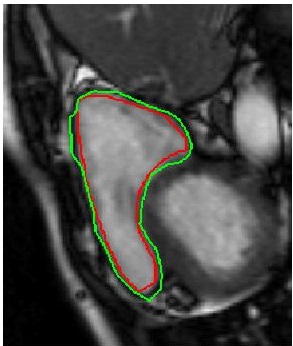

Table 2 summarizes the performance of different methods, and Figure 3 shows superimposed manual contour of the RV (red) and the deformed contour of the registered image (green). Better registration is reflected by closer alignment of the two contours. Once again it is obvious that has the best performance amongst all competing methods, and its advantages over when including deformation consistency.

| (a) | (b) | (c) | (d) |